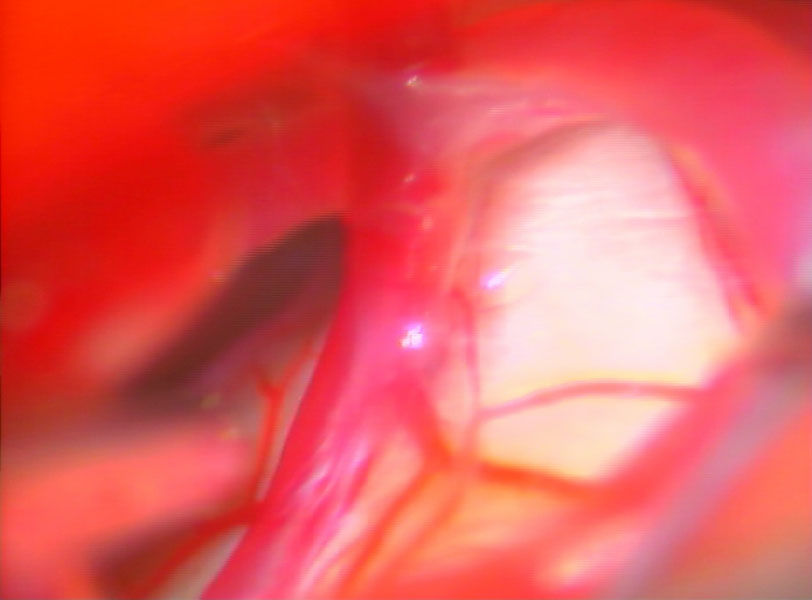

手術中

処置後